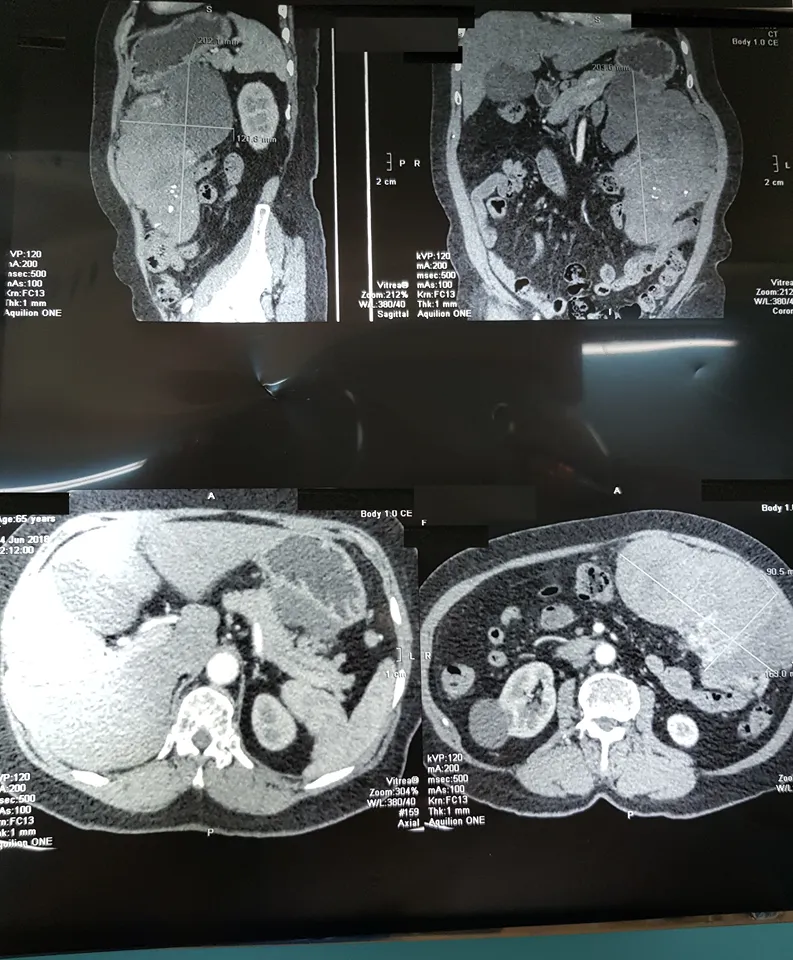

Kết quả siêu âm cũng cho thấy một khối u kích thước lớn, chưa rõ bản chất. Bên cạnh đó, kết quả CT scan khảo sát vùng bụng phát hiện khối u mô đệm thành dạ dày, choán chỗ toàn bộ vùng hạ sườn trái, có đường kính lớn nhất lên tới 20 cm. Ngay lập tức bà L. được chuyển đến Bệnh viện Bình Dân để nội soi dạ dày-tá tràng, kết quả cho thấy một khối u dưới niêm mạc dạ dày dạng u mô đệm đường tiêu hóa (GIST-Gastrointestinal Stromal Tumor).